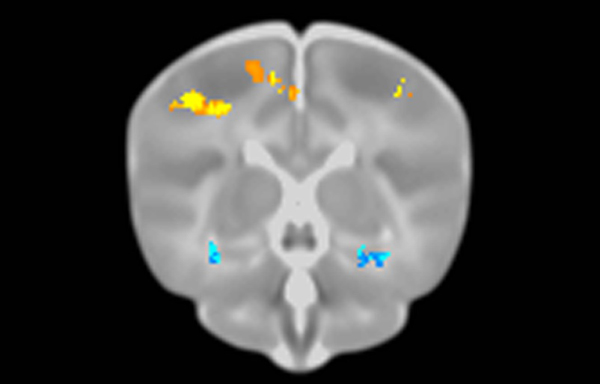

Brains of newborns with some versions of these genes had features similar to those seen in the brains of adults with diseases, the team found. Newborns with the ε4 version of the ApoE gene had less brain tissue volume in the temporal cortex, a part of the brain that thins in elderly people and adults who have ε4. Newborns with a variant in COMT also had reduced volume in the temporal cortex, a brain characteristic that turns up in people with schizophrenia.